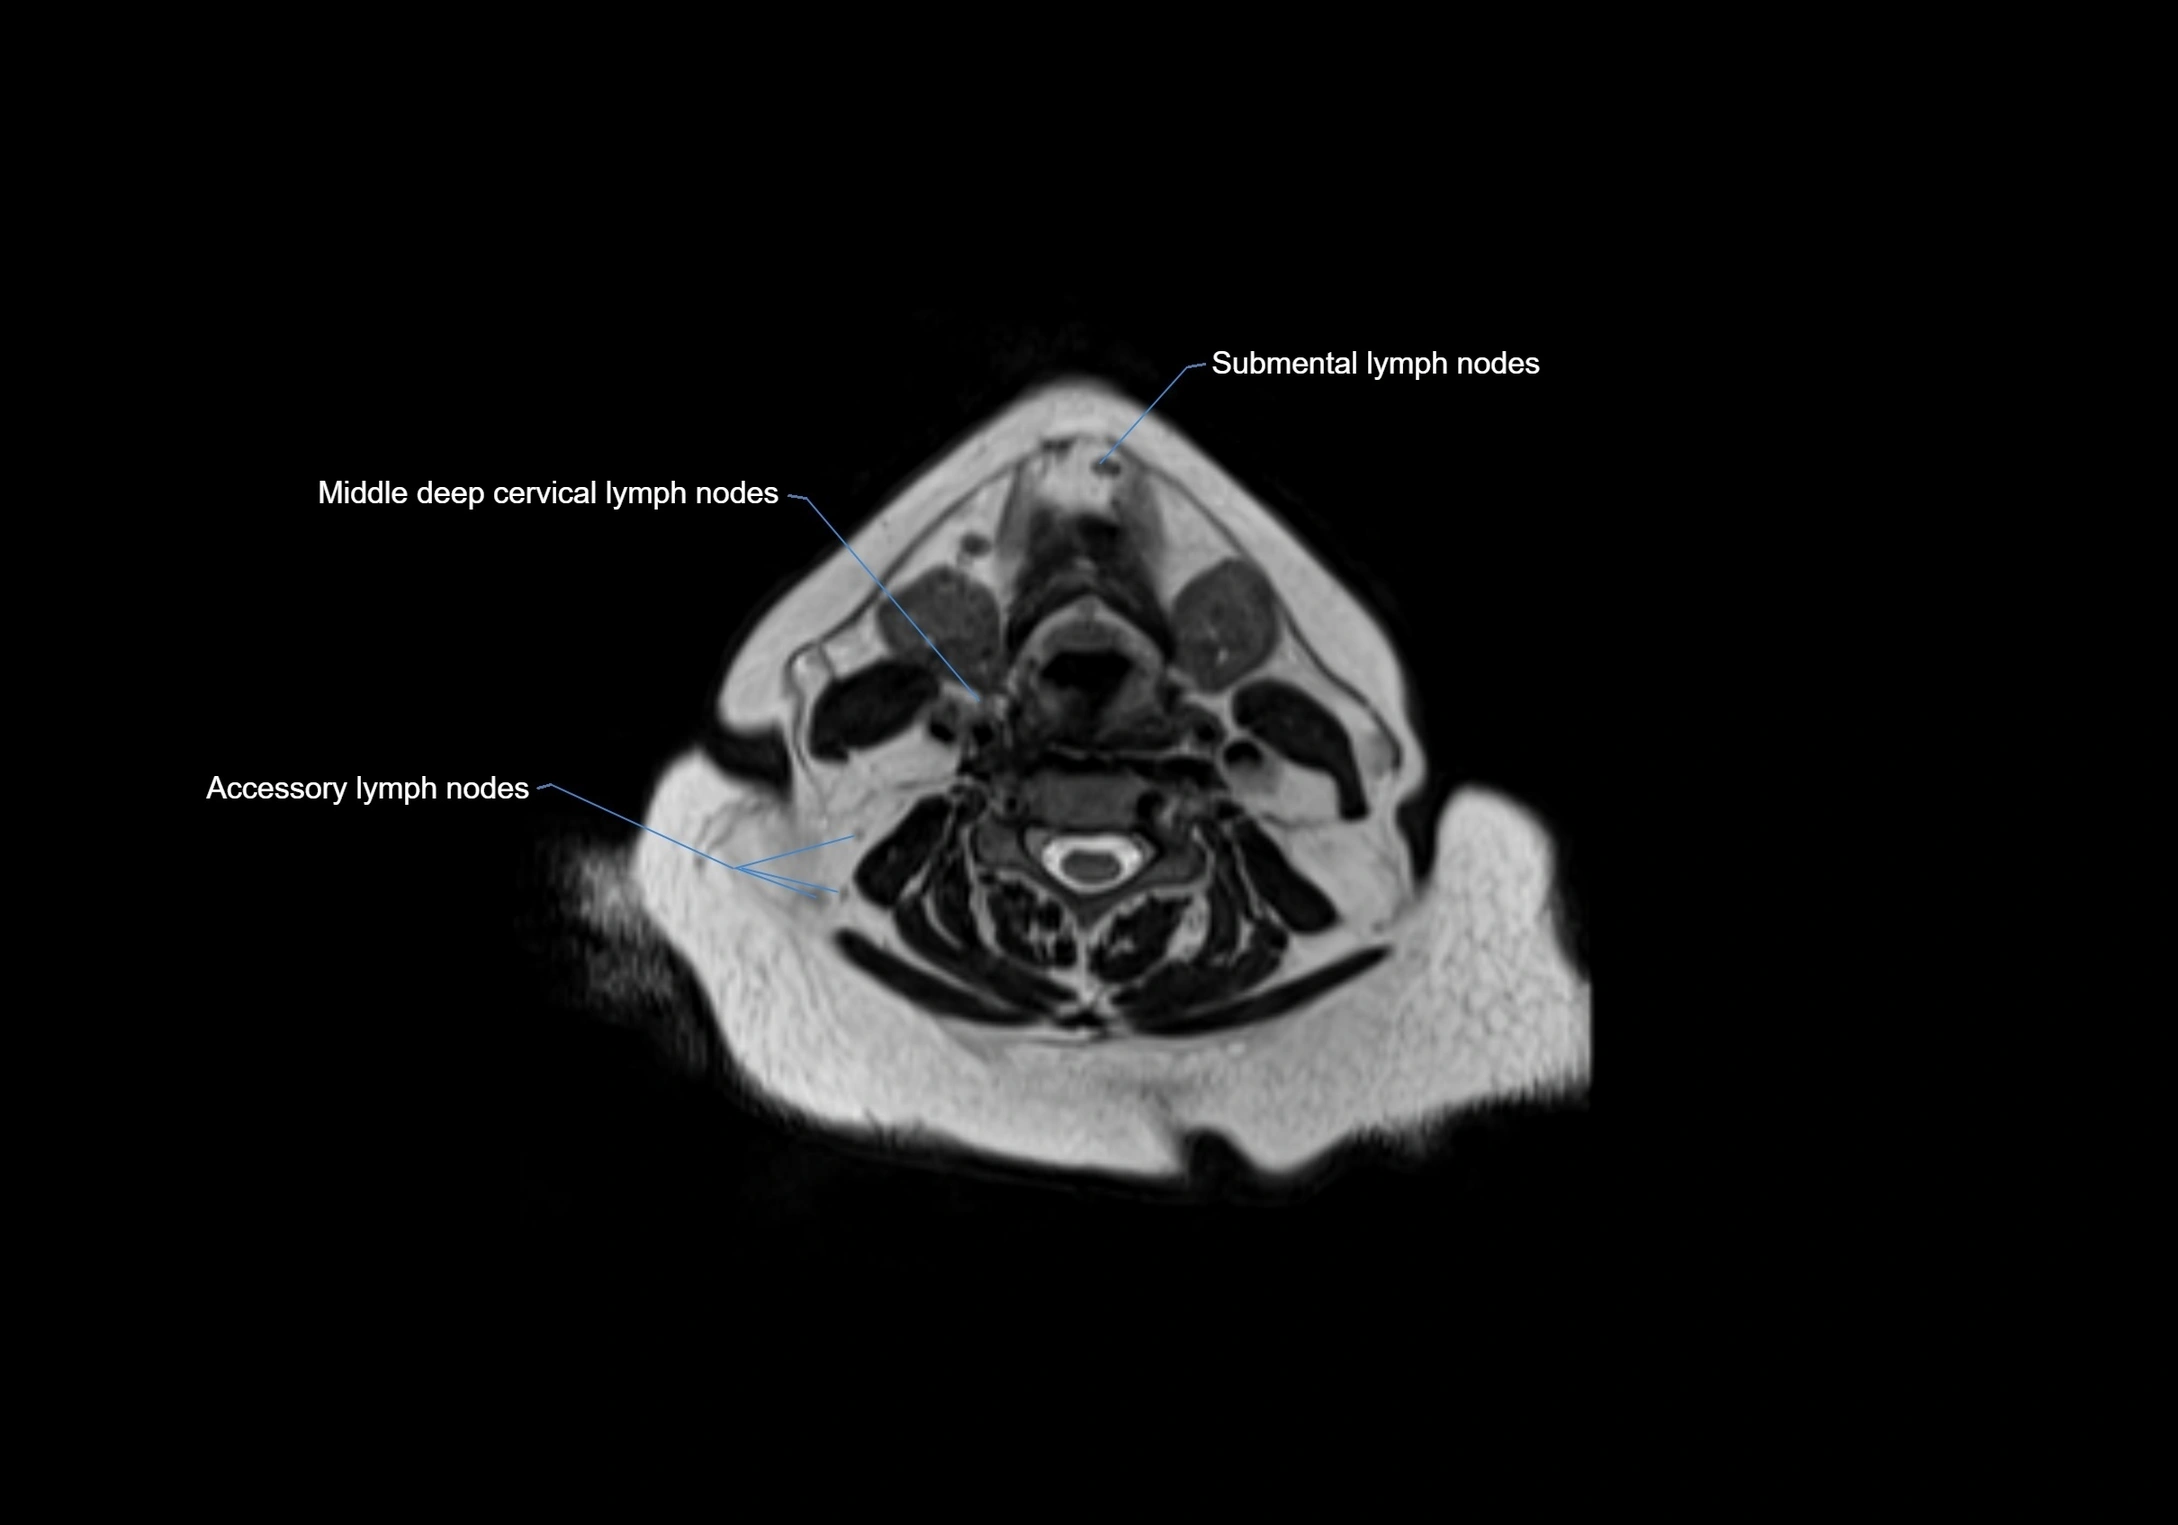

Accessory lymph nodes

Accessory lymph nodes are small, secondary lymph nodes located along the main facial and cervical lymphatic chains, often adjacent to primary lymph nodes, such as preauricular, submandibular, or occipital nodes. They are typically less than 5 mm in diameter, embedded within subcutaneous fat or connective tissue, and may be variable in number and location. These nodes provide additional filtration and immune surveillance for lymph collected from the face, scalp, and neck regions. Accessory lymph nodes are usually non-palpable in healthy individuals but may enlarge in response to infection, inflammation, or metastasis, making them clinically significant.

Location

• Found along primary lymph node chains, including preauricular, submandibular, parotid, and occipital regions

• Embedded in subcutaneous fat or superficial fascia, often lateral or posterior to primary nodes

• Variable in number; may occur unilaterally or bilaterally, depending on individual anatomy

MRI Appearance

T1-weighted images:

• Normal accessory nodes appear as small, oval hypointense to intermediate signal structures within subcutaneous fat

• Surrounded by hyperintense fat, enhancing contrast for visualization

• Pathological nodes may appear enlarged or rounded, sometimes with cortical thickening

T2-weighted images:

• Nodes show intermediate signal, with surrounding fat bright

• Useful for detecting edema, inflammation, or infiltration

• Fatty hilum may appear slightly hyperintense relative to cortex

MRI images

image